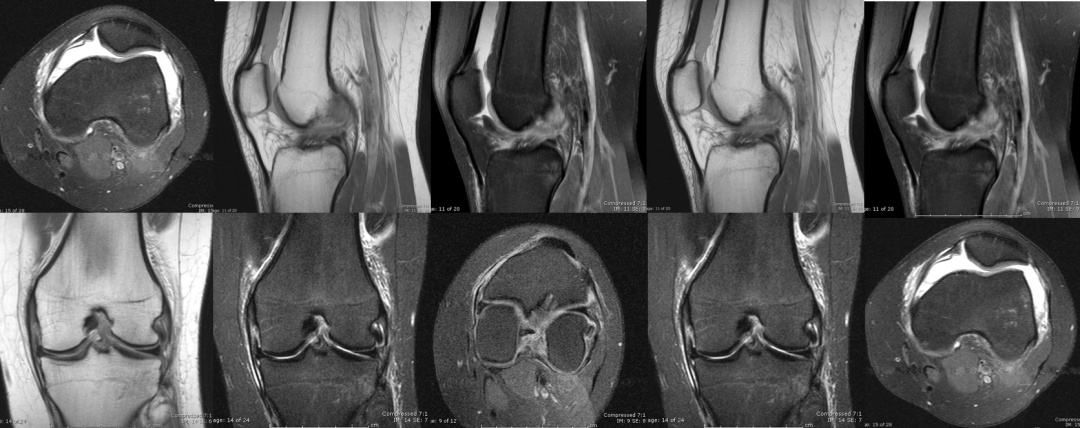

图 7 半月板损伤

除了韧带可能在运动中被扯断、撞坏之外,膝关节里还有两块半月板也很容易受伤。就像坐在硬板凳上屁股硌得难受一样,膝关节上下两个大骨头要是直接硬碰硬,你的膝关节肯定不会好受。而半月板就像两块缓冲垫,能让股骨和胫骨和谐共处,你的膝关节也能正常发挥功能。不过,如果半月板出现了损伤,那你的膝关节可能就不会那么灵活,蹲下站起可能会“咔咔”响,甚至有时好像卡住了一样。这时,MRI也是诊断的重要工具,如果真的存在半月板撕裂,在膝关节MRI上就能看到半月板“裂开”了。